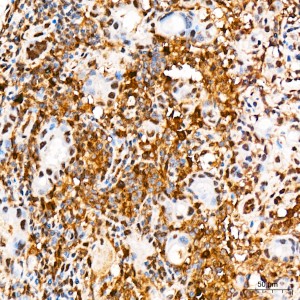

| Immunohistochemistry analysis of paraffin-embedded Human breast tissue using [KO Validated] STAT3 Rabbit mAb (A19566) at a dilution of 1:200 (40x lens). High pressure antigen retrieval was performed with 0.01 M citrate buffer (pH 6.0) prior to IHC staining. |

| Immunohistochemistry analysis of paraffin-embedded Human thyroid cancer tissue using [KO Validated] STAT3 Rabbit mAb (A19566) at a dilution of 1:200 (40x lens). High pressure antigen retrieval was performed with 0.01 M citrate buffer (pH 6.0) prior to IHC staining. |

| Immunohistochemistry analysis of paraffin-embedded Human brain tissue using [KO Validated] STAT3 Rabbit mAb (A19566) at a dilution of 1:200 (40x lens). High pressure antigen retrieval was performed with 0.01 M citrate buffer (pH 6.0) prior to IHC staining. |